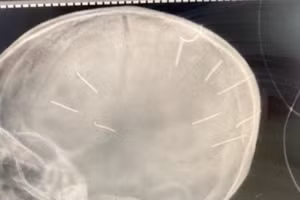

GD&TĐ - Cục Trẻ em (Bộ Lao động-Thương binh và Xã hội) vừa có công văn đề nghị Công an thành phố Hà Nội nhanh chóng chỉ đạo, điều tra vụ bé gái 3 tuổi nghi bị nhiều đinh găm vào hộp sọ.